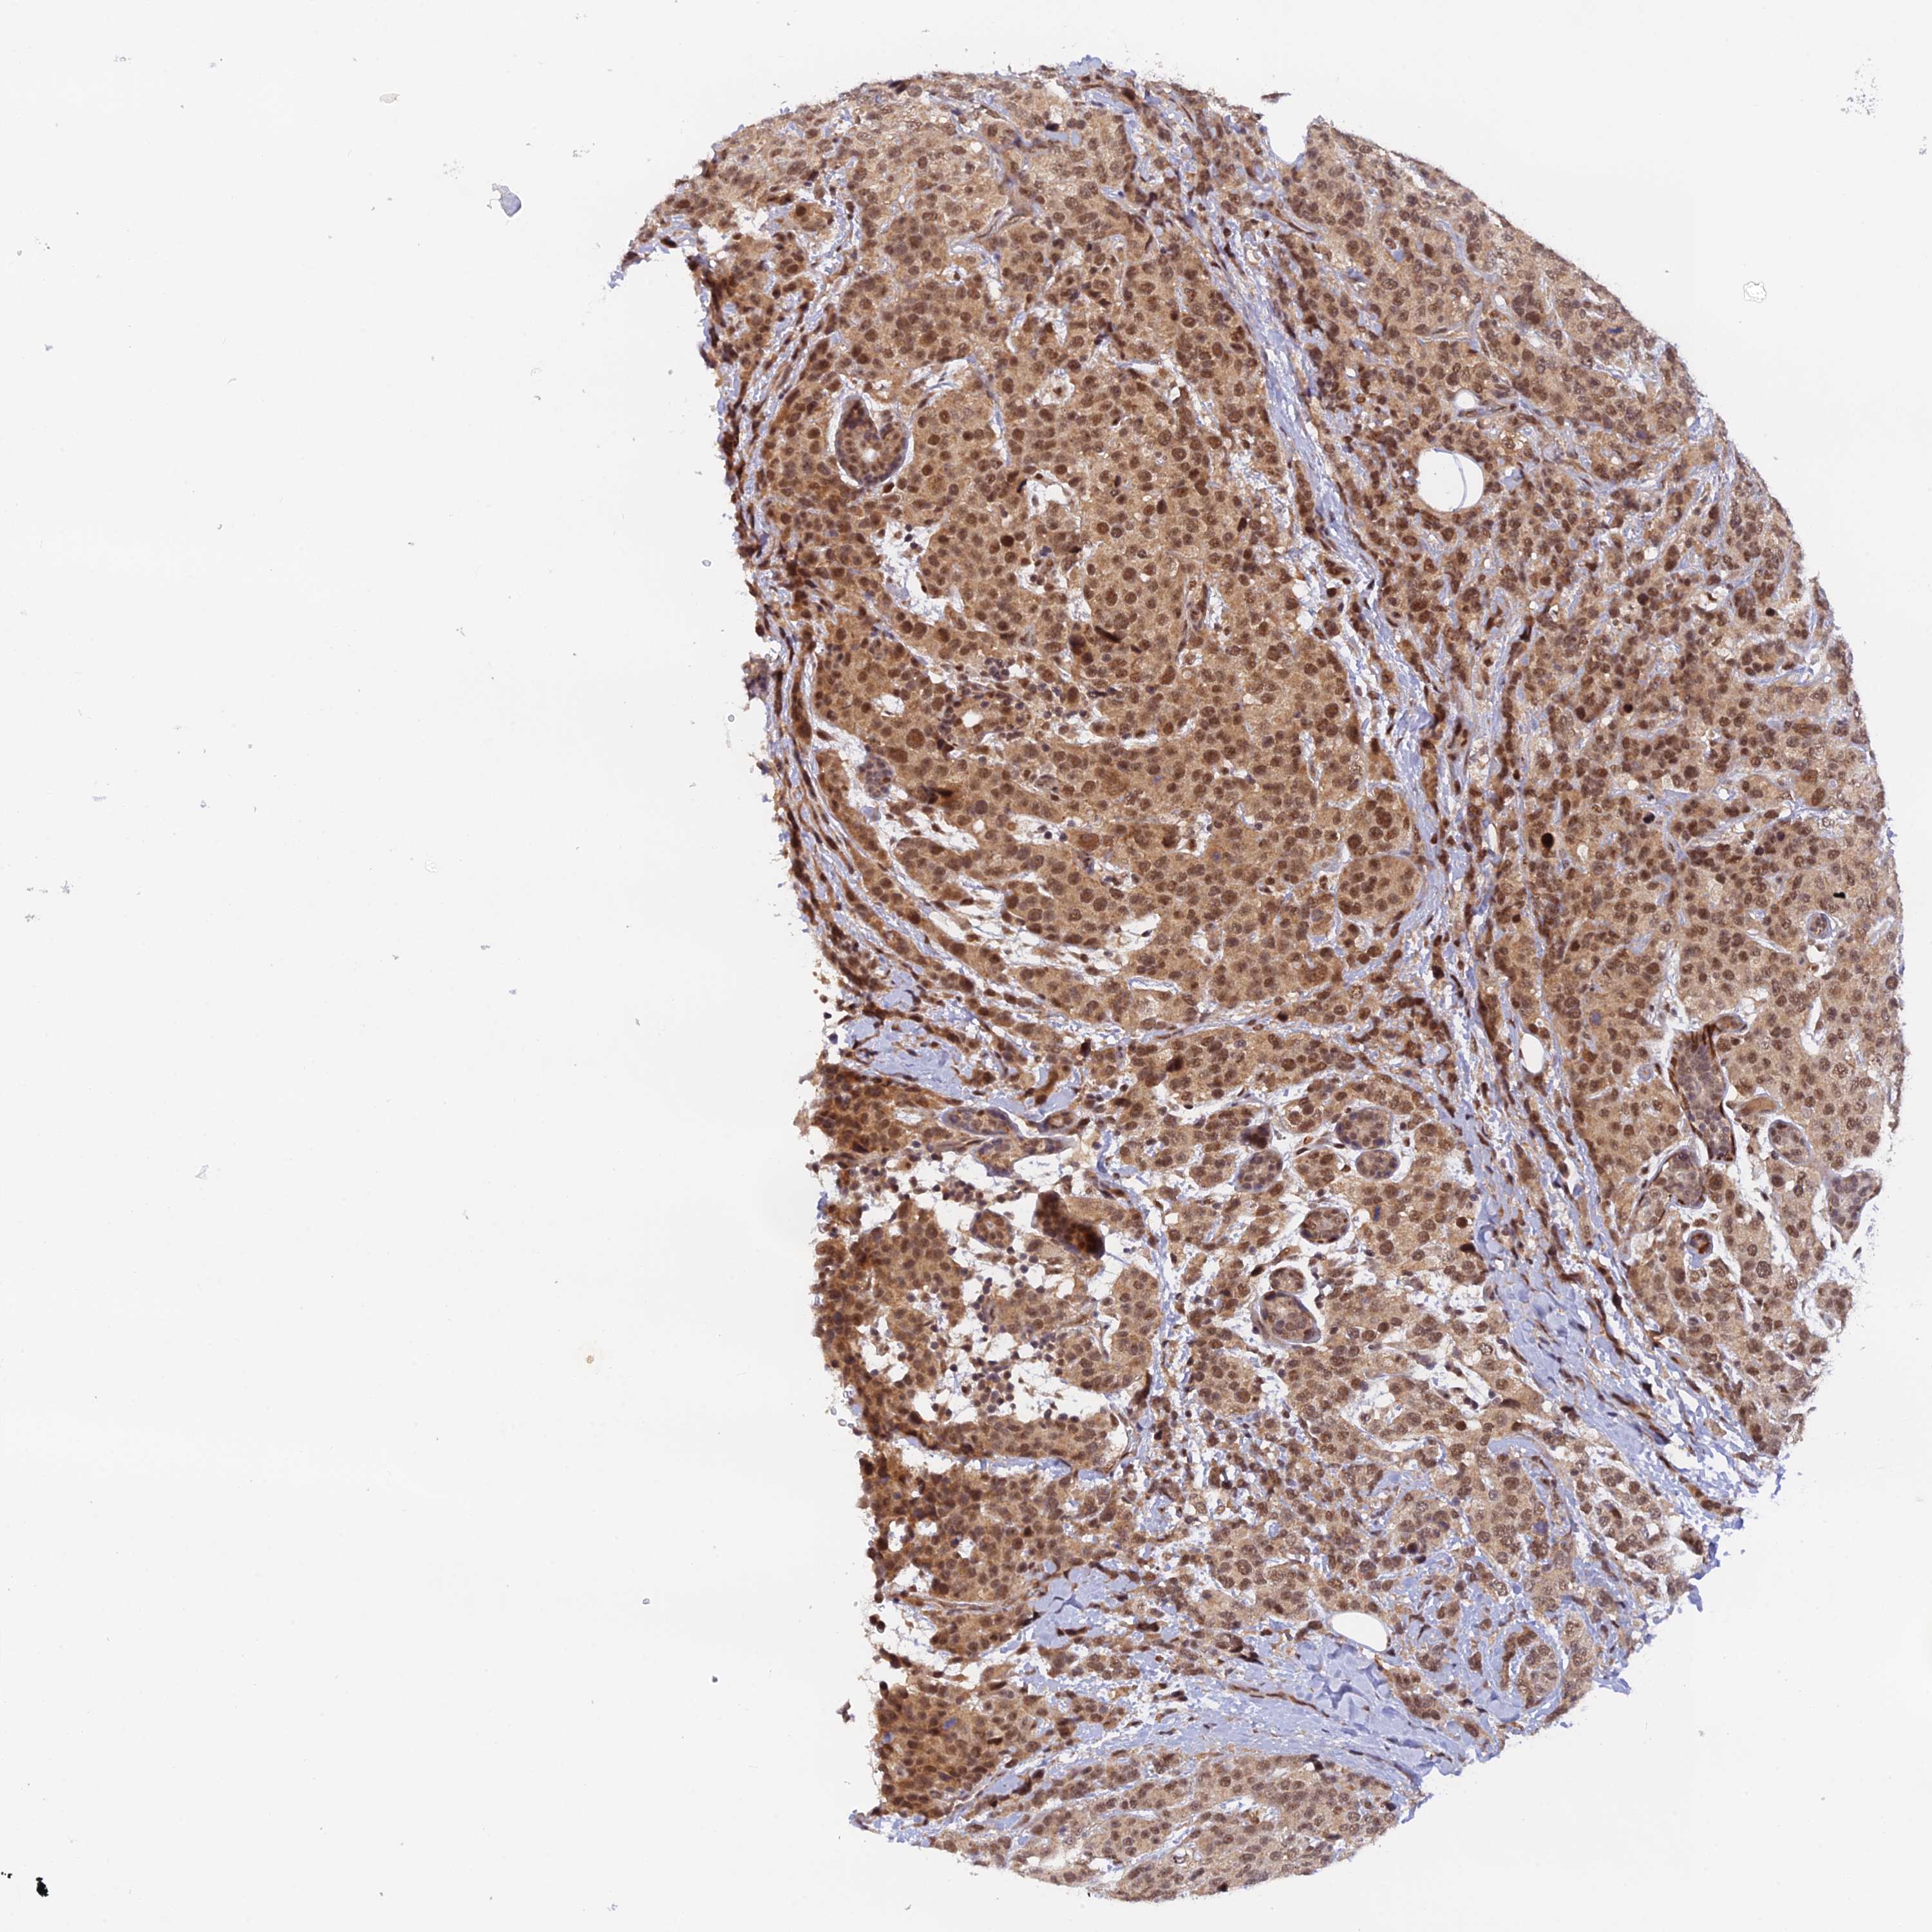

BRCA TCGA BRCA VALIDATION PROTEIN EXPRESSION